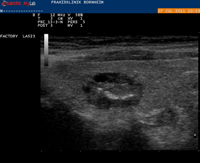

Die wichtigste Untersuchungsmethode bei Verdacht auf einen Schilddrüsenknoten ist die Ultraschalluntersuchung der Schilddrüse. Bei der Schilddrüsen-Sonographie kann die Größe und Struktur der Schilddrüsenknoten dargestellt werden. Vor allen Dingen aber kann ein eventuelles Wachstum der Knoten bei Kontrolluntersuchungen gut erfasst werden. Eine Schilddrüsenszintigraphie mit radioaktiven Technetium-99 ist notwendig, wenn die Laborwerte Hinweise auf eine sog. Autonomie (heißer Knoten) ergeben. Dann ist das TSH erniedrigt und bei einer manifesten Überfunktion die Schilddrüsenhormone zusätzlich fT3 und fT4 erhöht. Eine Schilddrüsenszintigraphie ist unter Umständen auch erforderlich, wenn gleichzeitig mehrere Schilddrüsenknoten zu finden sind.

Mit der Schilddrüsensonographie kann man Hinweise auf eine mögliche Bösartigkeit des Knotens bekommen. Ein Schilddrüsenkarzinom ist meist echoarm (im Ultraschall dunkel) und größer als 1cm. Es finden sich in der Schilddrüsensonographie bei Bösartigkeit häufig Mikroverkalkungen und ein verwaschener Rand des Knotens. Weitere Faktoren, die das Risiko für ein Schilddrüsenkarzinom erhöhen sind: Alter unter 20 Jahre oder über 70 Jahre, männliches Geschlecht, rasches Knotenwachstum, vergrößerte Halslymphknoten oder anhaltende Heiserkeit sowie harte, schlecht von der Umgebung abgrenzbare Knoten. Auch wenn der Knoten tiefer als breit ist, kann dies ein Hinweis auf Bösartigkeit sein. Das seltene meduläre Schilddrüsenkarzinom (C-Zell-Karzinom) kann man mit einer Laboruntersuchung (Calcitonin) ausschließen.